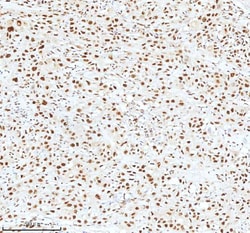

Reconstitute with 0.2 mL of distilled water to yield a concentration of 500 μg/mL. Positive Control - WB: human LNCAP whole cell, human Hela whole cell, human 293T whole cell, human HepG2 whole cell, human Jurkat whole cell, human K562 whole cell, human A549 whole cell, human A431 whole cell. IHC: human bladder cancer tissue, human bladder cancer tissue, human colon adenocarcinoma tissue, human colon adenocarcinoma tissue, human glioblastoma tissue, human glioblastoma tissue, human liver cancer tissue, human liver cancer tissue, human lung adenocarcinoma tissue, human lung adenocarcinoma tissue, human pancreas ductal adenocarcinoma tissue, human pancreas ductal adenocarcinoma tissue, human testicular seminoma tissue, human testicular seminoma tissue. ICC/IF: U2OS cell. Flow: A431 cell. Store at -20°C for one year from date of receipt. After reconstitution, at 4°C for one month. It can also be aliquotted and stored frozen at -20°C for six months. Avoid repeated freeze-thaw cycles.

| Flow Cytometry, Immunohistochemistry (Paraffin), Western Blot, Immunocytochemistry | |